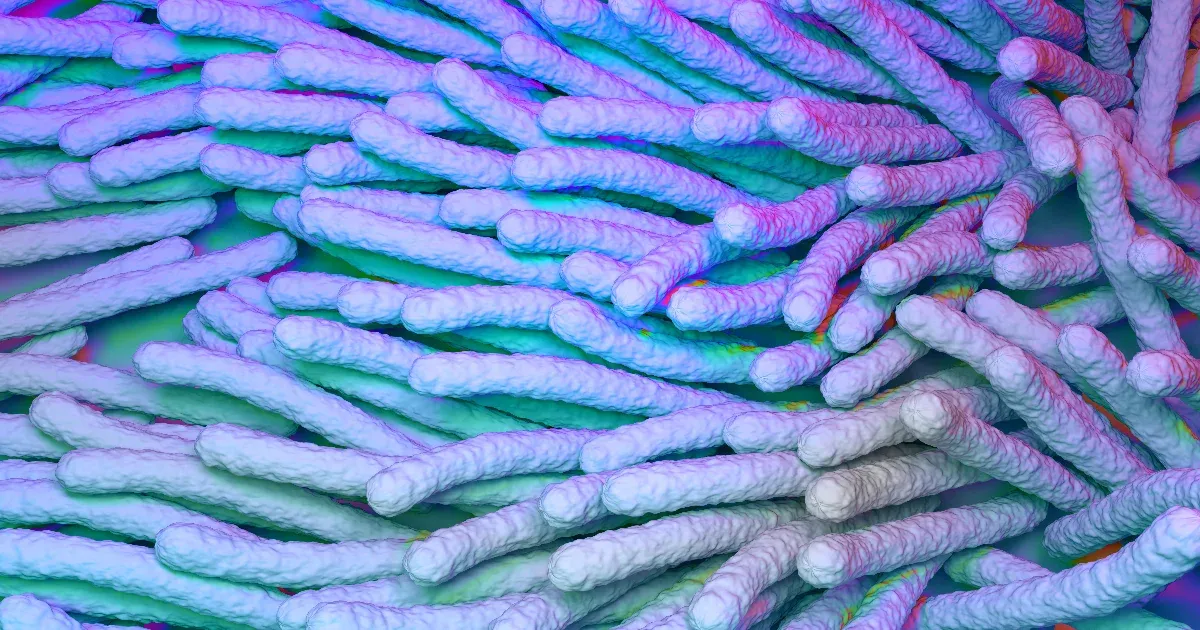

Tbc-fertőzés: ismét robbanásszerűen terjed a betegség

A tuberkulózis (tbc) újra fellendülőben van. 2023-ban a becslések szerint több mint 8 millió embert érintett a betegség; ez a legnagyobb növekedés az új esetek számában 1995 óta. Ráadásul nagy probléma, hogy a tbc kórokozója, a Mycobacterium tuberculosis kezd ellenállóvá válni a kezelésekkel szemben.